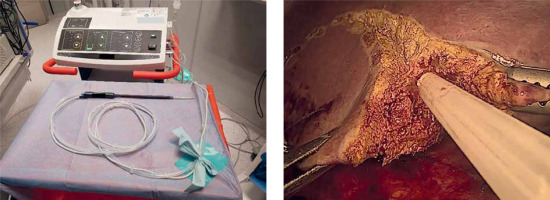

PM should be prepared before parenchymal transection for possible immediate application. It can be performed intracorporeally and extracorporeally. For an intracorporeal PM a long cotton tape is placed around the hepatoduodenal ligament through a 12 mm trocar, then passed through a small tourniquet and clipped 2–3 cm above it. For occluding the hepatic inflow, the tourniquet is pushed toward the hepatic pedicle and clipped above it. Pedicle clamping may also be performed with a laparoscopic bulldog clamp or appropriately prepared Foley’s catheter (Photo 3) [22]. For an extracorporeal PM the tape is externalized through a trocar and passed through the catheter placed above the trocar. The main advantage of the extracorporeal technique is the possibility for clamping by the assistant surgeon, without distraction of the main surgeon (Photo 4). When comparing both techniques of PM in retrospective studies, extracorporeal PM carries more practical advantages, but it still requires further research [23]. PM can be continuous or intermittent (most commonly 15 : 5 min ratio or 10 : 5 min ratio in cirrhotic liver). In HCC patients, according to a recent RCT, 25 min intermittent PM results in lower BL, as well as higher transection speed [24]. However, the performed PM technique depends on surgeons’ preferences and estimated operative time.

Nonetheless, in LLS, application of some TA may be challenging. Although there are no data addressing this issue, according to the clinical experience, sprays and powders are easier to apply via laparoscopy than sponge-based local TA (Photo 8).